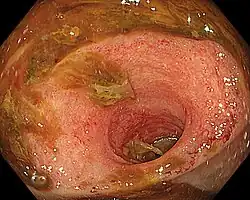

| Ileitis caused by capecitabine. | |